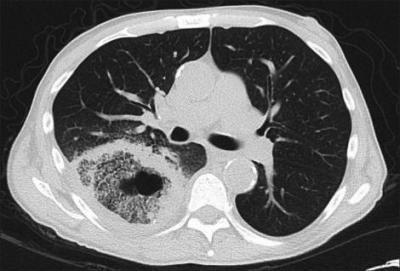

-फुफ्फुसांचा म्युकोरमायकोसिस- बुरशीचे सूक्ष्मकण श्वासावाटे शरीरात शिरून श्वसनसंस्थेत पोहोचतात तेव्हा त्यांचा फुफ्फुसांवर परिणाम होतो. ताप, छातीत दुखणे, खोकला, खोकल्यातून रक्त पडणे ही यायची लक्षणे आहे.